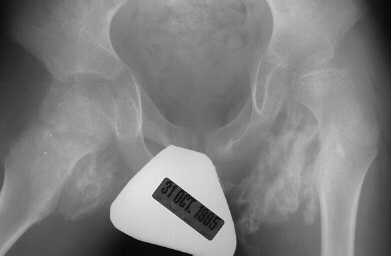

A nine year old male with a diagnosis of spastic quadriplegic,

cerebral palsy presented for a follow-up exam. This patient was

non-ambulatory and non-verbal. Patient had good head control and

was capable of sitting if propped up. The patient had bilateral

release of iliopsoas, gracilis, adductor longus, distal hamstrings

and right tensor facia lata release 4 weeks prior to this examination.

Now, the patient still required valium and analgesics due to pain

and muscle spasms. At this time a firm mass was palpated in the

left groin. The whole groin was warm to touch and the child was

reported to have intermittent temperature elevation to 38.5 degrees.

He appetite was also diminished. Two months post op the patient

was still having pain. Four months post op the patient was more

comfortable but still having pain with motion at (the end of his

range) 90 degrees flexion, -30 degrees extension, 20 degrees of

abduction and no rotation.

Heterotopic

ossification which forms after hip surgery in children with Cerebral

Palsy usually requires surgical excision followed by radiation

treatment.

ossification occurs more commonly in children with CP in the area

of the iliopsoas or when hip surgery is done in close temporal

proximity to spinal surgery.